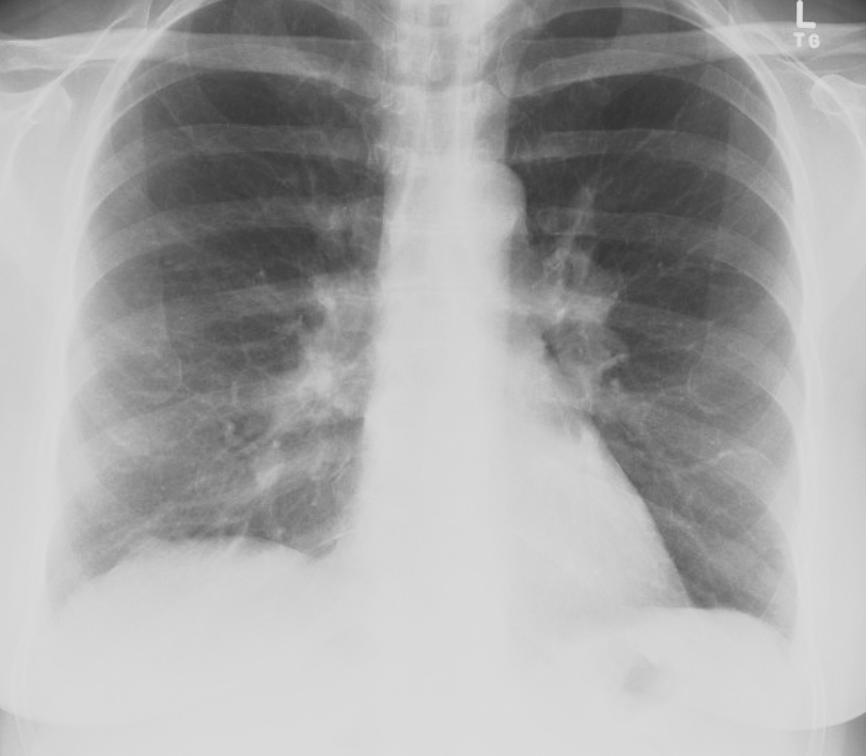

Bilateral enlargement of hilar nodes occurs in: triad

• Malignant lymphoma.

• Tuberculosis.